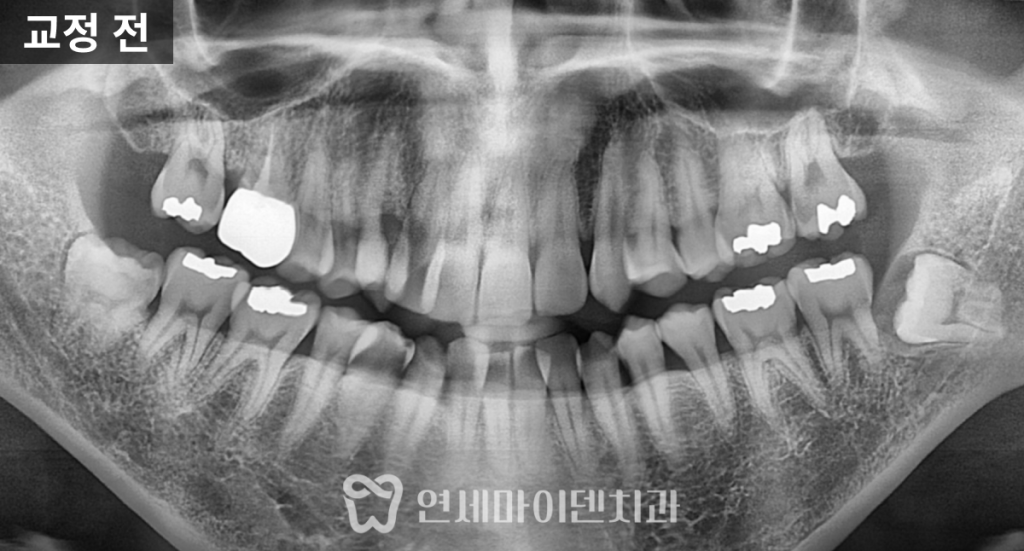

파노라마 방사선 사진을 통해 치아의 상태를 더 정밀하게 확인했습니다.

전체 치아 갯수는 결손 없이 정상이었고

아래쪽에만 2개의 매복 사랑니가 있었습니다.

치아의 공간이 부족했지만 비발치 교정을 원하셔서

매복 사랑니를 발치해서 아래턱의 공간을 확보한 뒤 치아의 재배열이 필요했습니다.